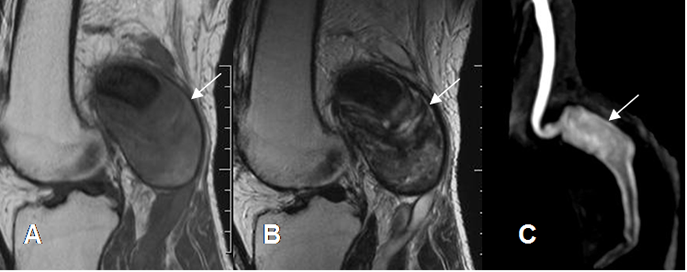

Son masas pulsátiles, con bordes calcificados en la Rx. Tienen continuidad con un vaso, señal doppler en su interior y ausencia de flujo en RM, si no está trombosado. (Fig 216).

Fig 216. Lesión vascular.

A: RM sagital en T1 y B: RM sagital en T2. Imagen ovalada que ocupa la fosa poplítea, de señal heterogénea.

C: AngioRM con contraste. Se confirma la formación de un aneurisma de la poplítea, el cual está parcialmente trombosado.